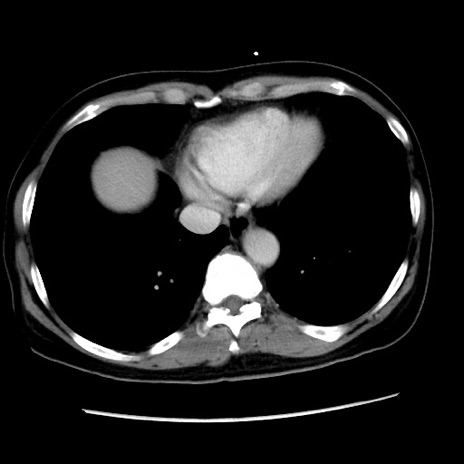

症例10(横断像)

【症例】 50歳代女性

【主訴】 腹痛

【現病歴】前日生レバーを食べた。今朝に排便あり。 昼前に突然発症の腹痛を生じ、当院救急外来を受診した。

【既往歴】 子宮筋腫にてで子宮全摘後

【身体所見】 意識清明、腹部:平坦、軟、下腹部やや左を中心に圧痛・反跳痛あり、筋性防御あり

【データ】WBC 7800、CRP 0.07